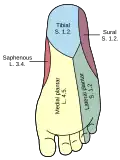

Nerfs cutanés du membre inférieur droit. Vues de face et de derrière. Diagramme de la distribution segmentaire des nerfs cutanés de la plante du pied.

Diagramme de la distribution segmentaire des nerfs cutanés de la plante du pied. Nerfs profonds à l'avant de la jambe.